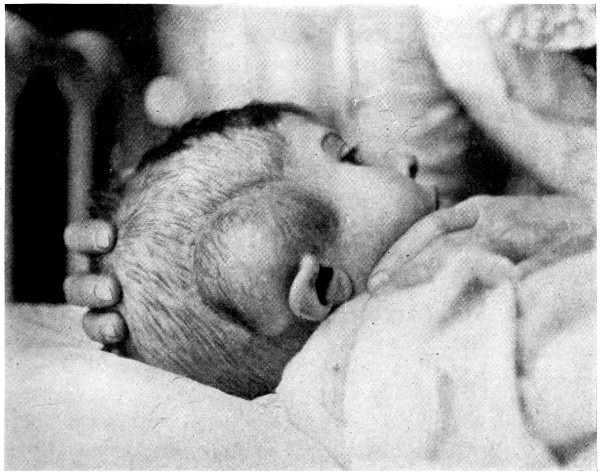

| 24 A and B. A case of depressed birth-fracture, before and after operation | 47 |

| 25. To illustrate the effects and position of a birth-hæmorrhage | 53 |